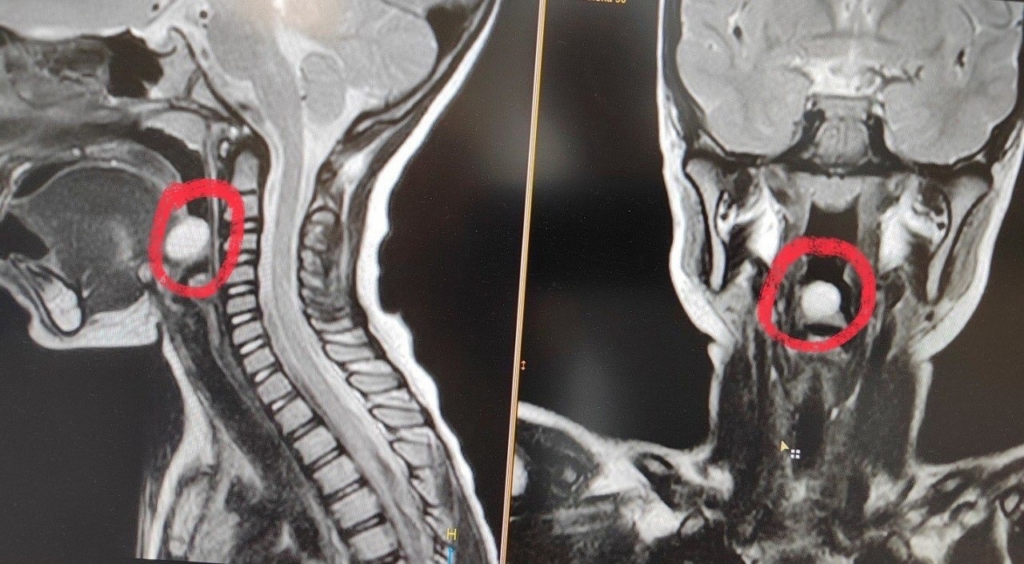

В начале года в оториноларингологическое отделение Воронежской областной детской клинической больницы №1 (ВОДКБ №1) поступила 5-летняя девочка с жалобами на затруднение при глотании. При профилактическом осмотре ЛОР-врач заподозрил новообразование надгортанника и направил в дневной стационар онкогематологии ВОДКБ №1. Там врачи провели ребенку эндоскопическое обследование и МРТ с контрастированием, что позволило определить диагноз: киста надгортанника. Медики приняли решение об эндоскопическом удалении новообразования.

Отметим, что киста надгортанника часто выявляется случайно. При увеличении размеров этого доброкачественного новообразования у пациента возникают ощущение инородного тела в горле и дискомфорт при глотании.